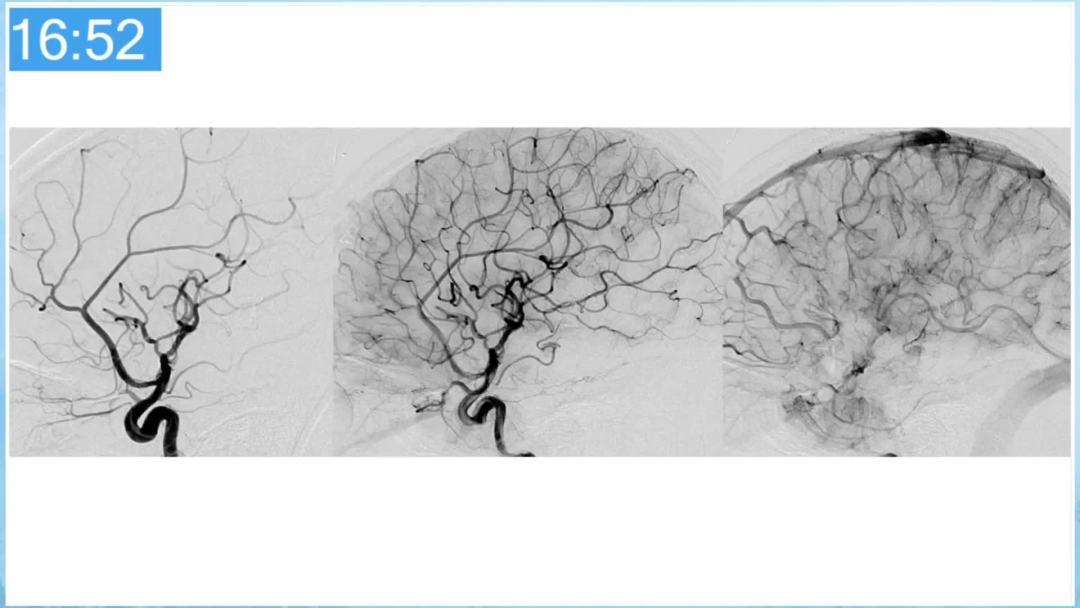

合理的复合平台下的综合治疗,针对每一个病变对应不同方法安全性分析,不预设、不排斥,每种技术发挥到最佳,互相保障。

本期为大家特别分享:空军军医大学唐都医院邓剑平教授的精彩会议内容《颅内动静脉畸形的复合手术治疗》,欢迎大家阅读和分享!